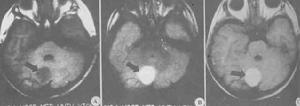

在x—cT像上,原始纖維型星形細胞瘤一般呈均一的低密度改變,合有較大的囊性結構,囊壁上常出現典型的瘤結節,增強時更清楚。瀰漫性星形細胞瘤在x—cT上呈等或低密度,邊界不清,增強不均一。MRI像上,兩者的實體部分在T1像呈低信號,兒像呈高信號,囊腔的信號依蛋白含量而定。囊腔中也可有出血所致的信號,但很少見。囊壁結節在注入增強劑後,立即出現增強效應。整個囊壁增強少見,一旦出現,可提示病灶的大致邊緣。MN定性診斷星形細胞瘤較x—cr優越,表現在:⑦可顯示浸潤性生長;②可判斷腦幹、小腦腳是否受侵犯。低惡性小腦星形細胞瘤,在發病早期很少發生腦脊液播散,不需要行全腦、脊髓MM及腦脊液細胞學檢查。